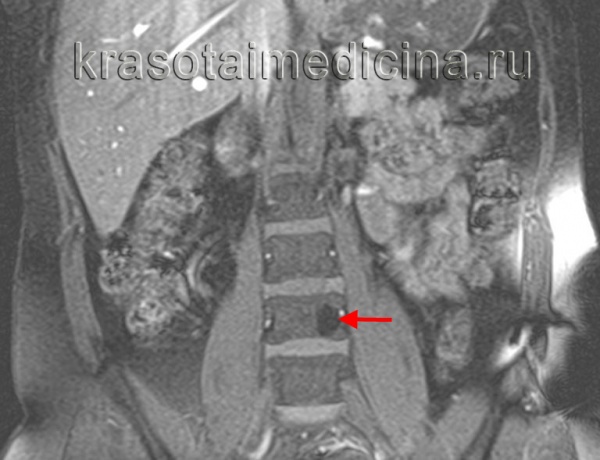

- Томография позвоночника. Для уточнения характера и степени поражения костных структур и мягких тканей после рентгенографии больного направляют на КТ или МРТ позвоночника. По данным МРТ определяется гипер- или изоинтенсивный испещренный сигнал на Т1- и Т2-взвешенных изображениях. По результатам КТ позвоночника выявляется образование с ячеистой структурой, по виду напоминающей соты.